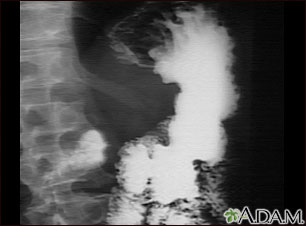

An upper GI series in a patient with cancer of the stomach (gastric carcinoma).